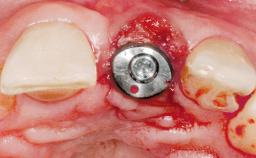

Immediate Flapless Placement of an Implant in a Maxillary Right Lateral Incisor Site

This 43-year-old male patient, a non-smoker, came to our practice because of a fracture of tooth 12 caused by a bicycle accident. Due to the combined para- and infrabony crown and root fracture, tooth extraction, and subsequent implant placement were suggested to the patient as the therapy of choice. The patient had high esthetic expectations with regard to the treatment outcome and asked for an immediate fixed provisional restoration. His individual esthetic risk profile summed up to a medium esthetic risk.

Placement Protocol Immediate implant placement

Tooth Site Maxillary incisor or canine

Socket Morphology Single-root socket

Socket Integrity Sufficient, with intact bone walls

Bone Volume Sufficient, with intact walls

Loading Protocol Immediate